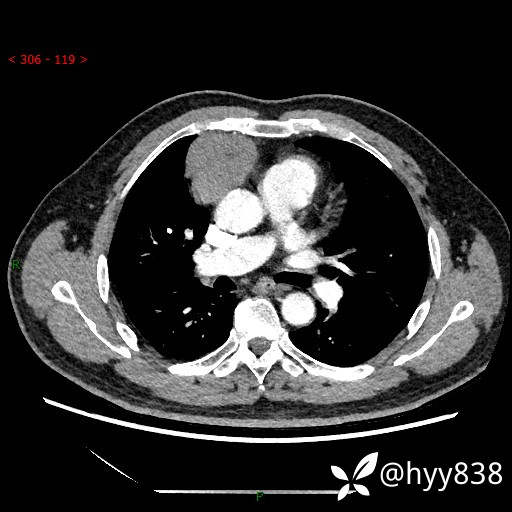

动脉期+静脉期

各期CT值